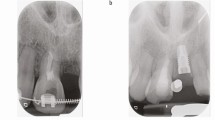

Results One hundred and fifty subjects were recruited. Mean age of the subjects was 11.1 years (SD = 2.6; range = 6.2-16.6); 100 were male and 50 were female. The mean time interval from injury until initial presentation to a health care professional was 22.6 hours (SD = 76.1; range = 0-672). Thirty-six percent of children (n = 54) first presented to a general dental practitioner whilst 30% (n = 45) presented to accident and emergency medical staff. Following initial assessment, a further mean time lapse of 8.1 hours (SD = 43.7; range = 0-504) was incurred in 25% of cases prior to dental referral. In 39% of subjects (n = 58/150), treatment was considered inappropriate. The most frequent example of inadequate management was failure to protect exposed dentine, which was found for 71% (n = 24/34) of complicated crown fractures and 40% (n = 25/62) of uncomplicated crown fractures.